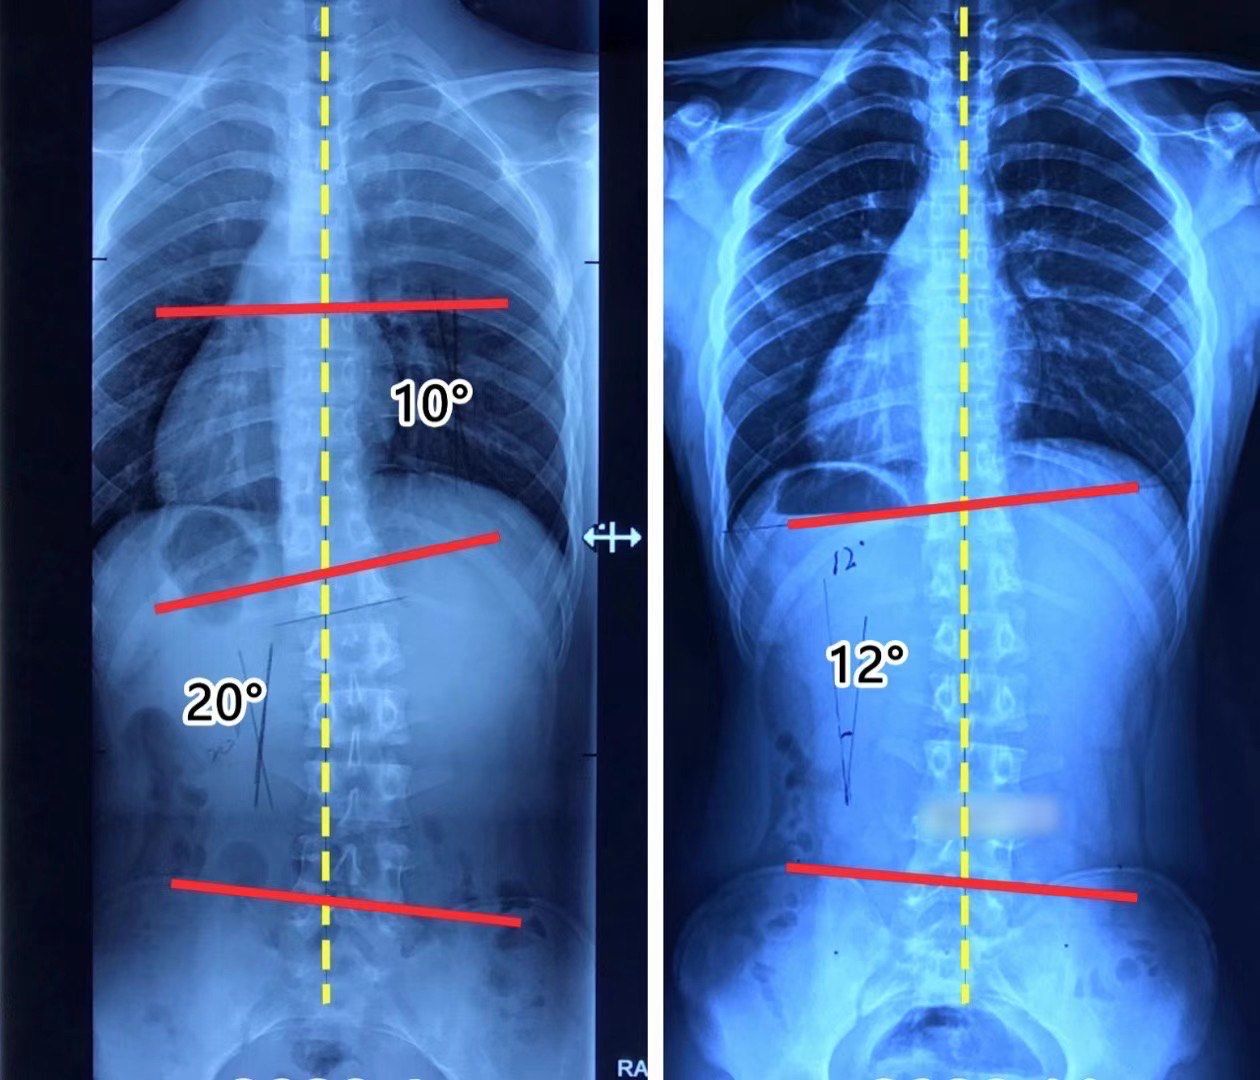

又是一例青少年重度脊柱侧弯案例,16岁男孩发现脊柱侧弯5年

年仅12岁被家长发现两肩不等高,体态异常